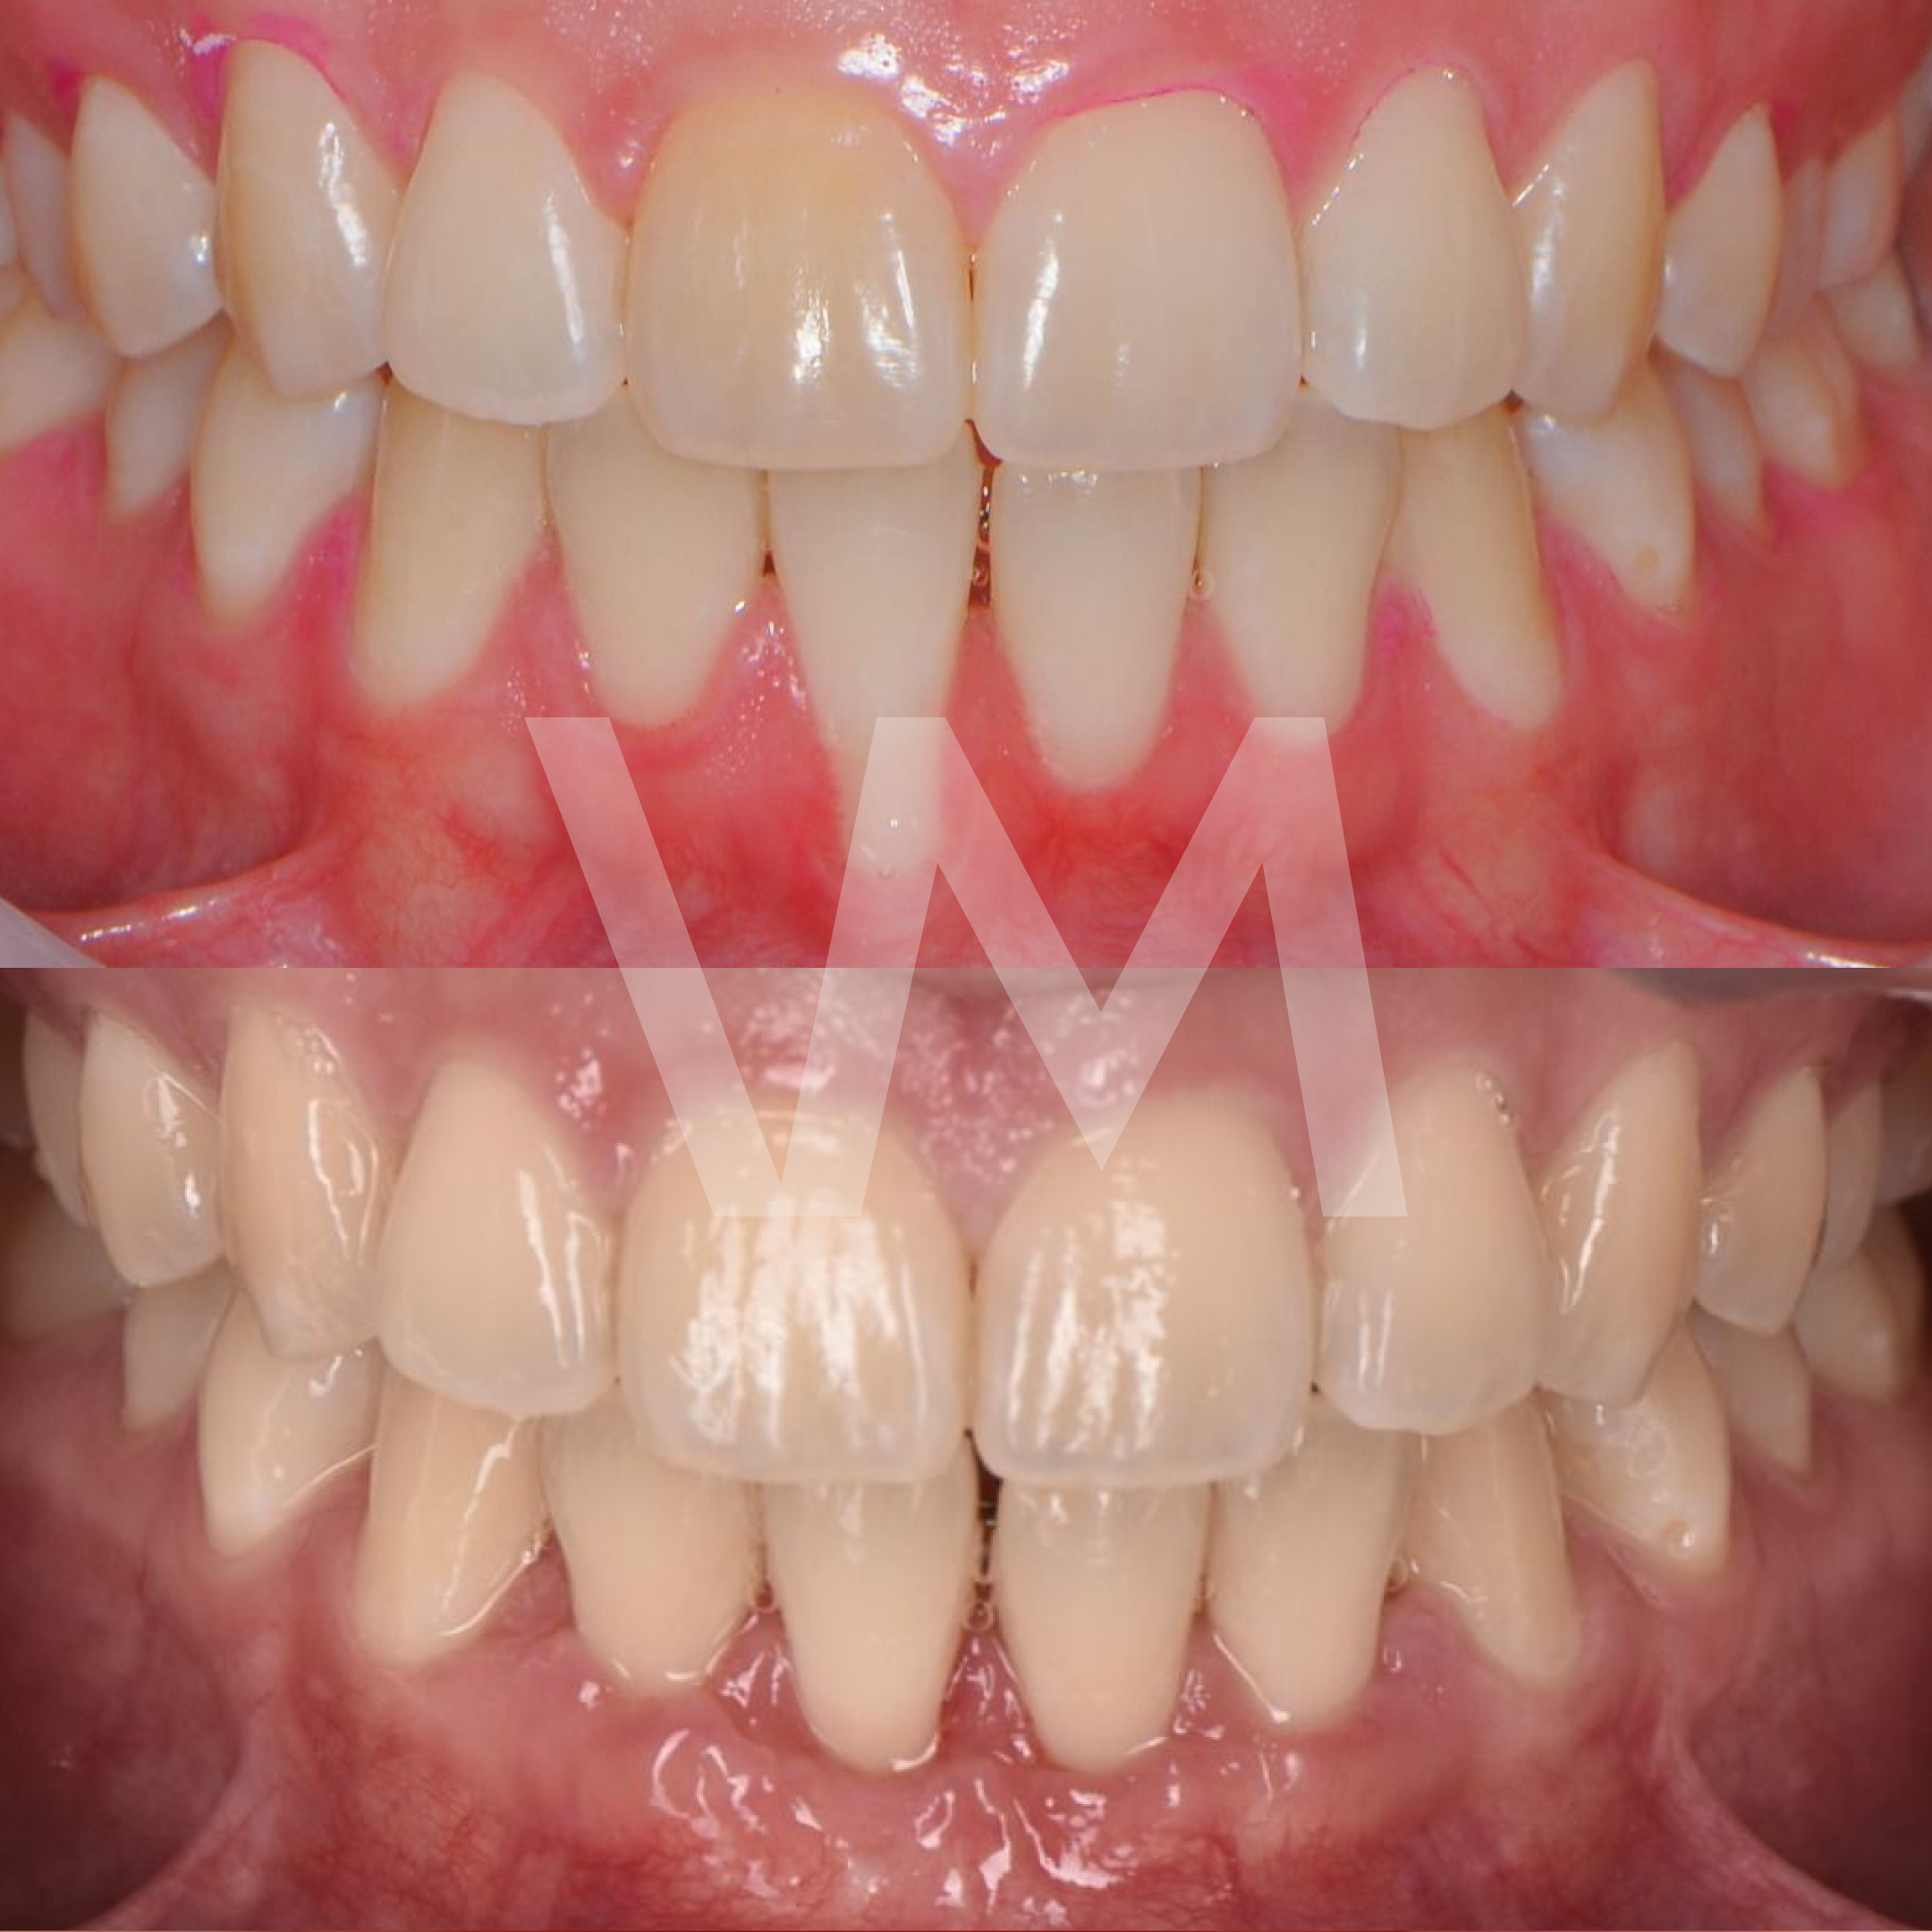

Injertos de encía

Cirugías de Injertos de Encía del Paladar e Injertos Sintéticos para el Tratamiento de Recesiones Gingivales

Las recesiones gingivales son un problema común en el que las encías retroceden, dejando expuesta la raíz del diente y aumentando el riesgo de sensibilidad dental, deterioro del hueso y pérdida de dientes. Para corregir estas recesiones y restaurar la salud gingival, se pueden realizar cirugías de injertos de encía del paladar e injertos sintéticos.

Beneficios de las Cirugías de Injertos de Encía:

- Mejora la salud gingival y previene la progresión de la recesión gingival.

- Reduce la sensibilidad dental causada por la exposición de la raíz del diente.

- Mejora la estética de la sonrisa al restaurar el contorno gingival natural.

Casos clínicos realizados por la Dra. Paulina